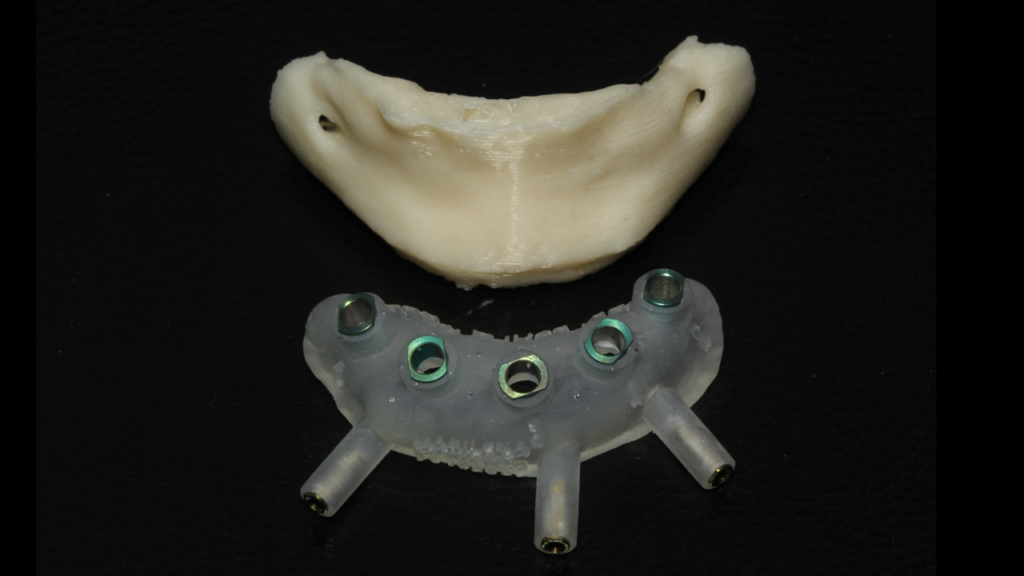

Através do programa Blue Sky (em parceria com a empresa Odontoplanning), foi feito planejamento guiado com 2 guias. O primeiro guia de recorte ósseo, tem como objetivo o recorte e aplainamento ósseo, deixando uma altura óssea mais uniforme entre a região posterior e anterior da mandíbula.

Através da imagem do osso recortado é planejada a guia de perfuração que vai se encaixar de uma maneira perfeita no osso recortado.

Lembrando que essas guias serão apoiadas exclusivamente no osso, sem envolvimento de mucosa, portanto há que se fazer incisão e descolamento mucoperiostal suficiente para o encaixe da guia.